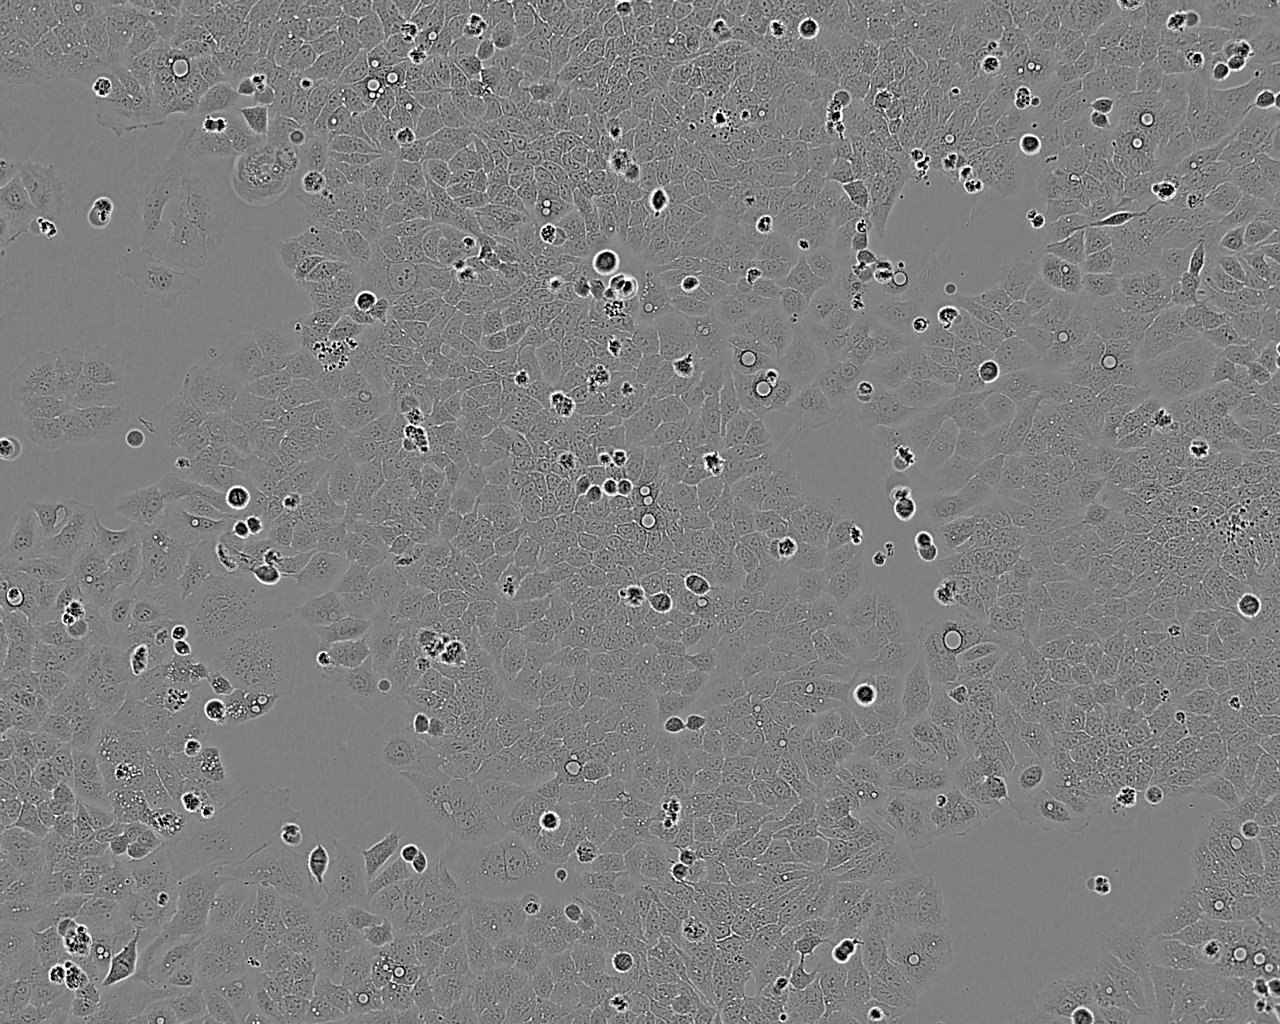

细胞形态:上皮细胞样

细胞生长:贴壁

细胞生长特性:贴壁生长